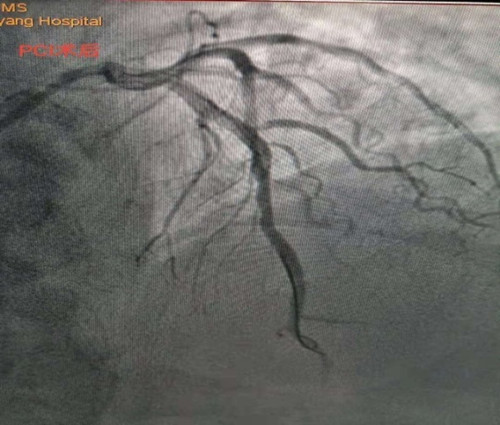

李新國主任為蒿大叔做了急診冠脈造影檢查,提示前降支近中段90%狹窄, D1開口99%狹窄,可見血栓影,結(jié)合術(shù)前心臟超聲檢查發(fā)現(xiàn)患者心臟腱索水平以下左室前間壁、前壁、前側(cè)壁運動搏幅減低,梗死范圍大,考慮罪犯血管為前降支近中段,在前降支近中段植入了一枚支架,開通閉塞血管。經(jīng)過1個多小時的搶救,蒿大叔總算從鬼門關(guān)被救了回來了。